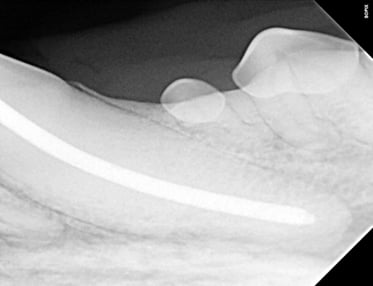

Below: Radiograph finding master file size to clean canal walls appropriately and find master cone size of gutta percha - note how spade of light speed file fills entire apex

Following thorough cleaning, a dry fit of gutta-percha was meticulously positioned, and a radiograph was taken to ensure precise placement.

Below: Radiograph dry fitting gutta percha to ensure fills space at apex